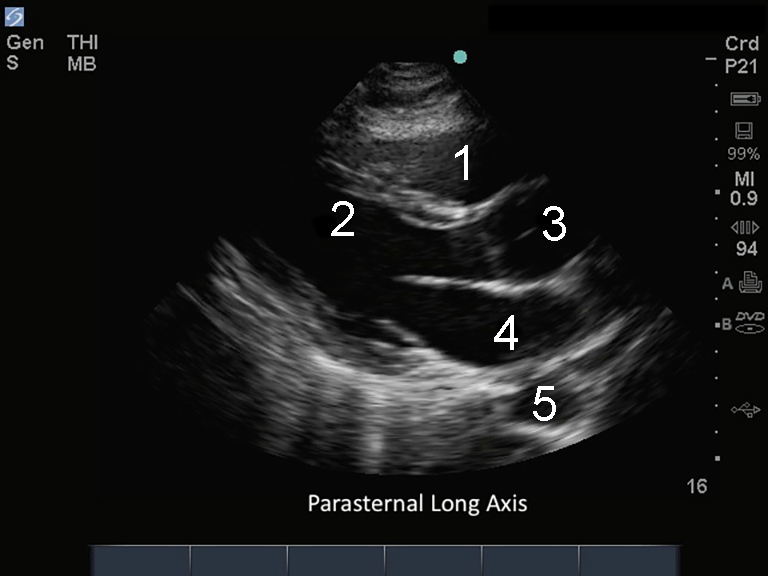

M-Turbo : Axe longitudinal parasternal

1. Ventricule droit (VD)

2. Ventricule gauche (VG)

3. Aorte (Ao) ascendante

4. • Oreillette gauche (OG)

5. Aorte (Ao) descendante